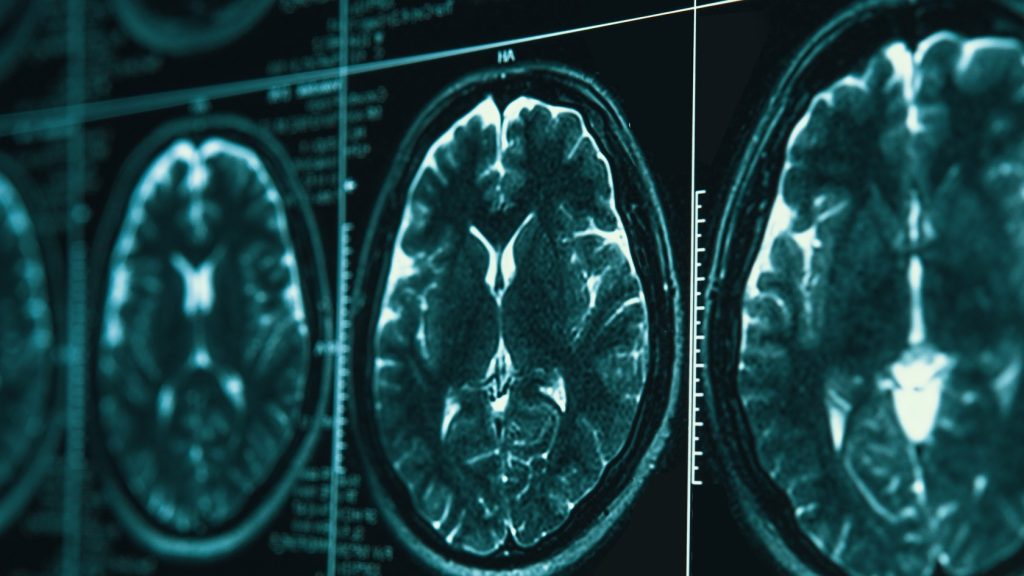

By the time symptoms begin creating problems, the disease has been unfolding in the brain for years. Microscopic amyloid-beta plaques have accumulated between neurons, and later threads of neurofibrillary tau proteins have tangled themselves into tight knots inside brain cells. The two abnormalities — first described in 1906 by the German physician Alois Alzheimer — have become the twin hallmarks of the disease.

But new technologies — artificial intelligence that may be able to identify new genetic determinants of the disease, blood tests for proteins in the brain, and real-time brain monitoring that reveals how individual neurons die — are finding new ways to understand and possibly help treat Alzheimer’s.